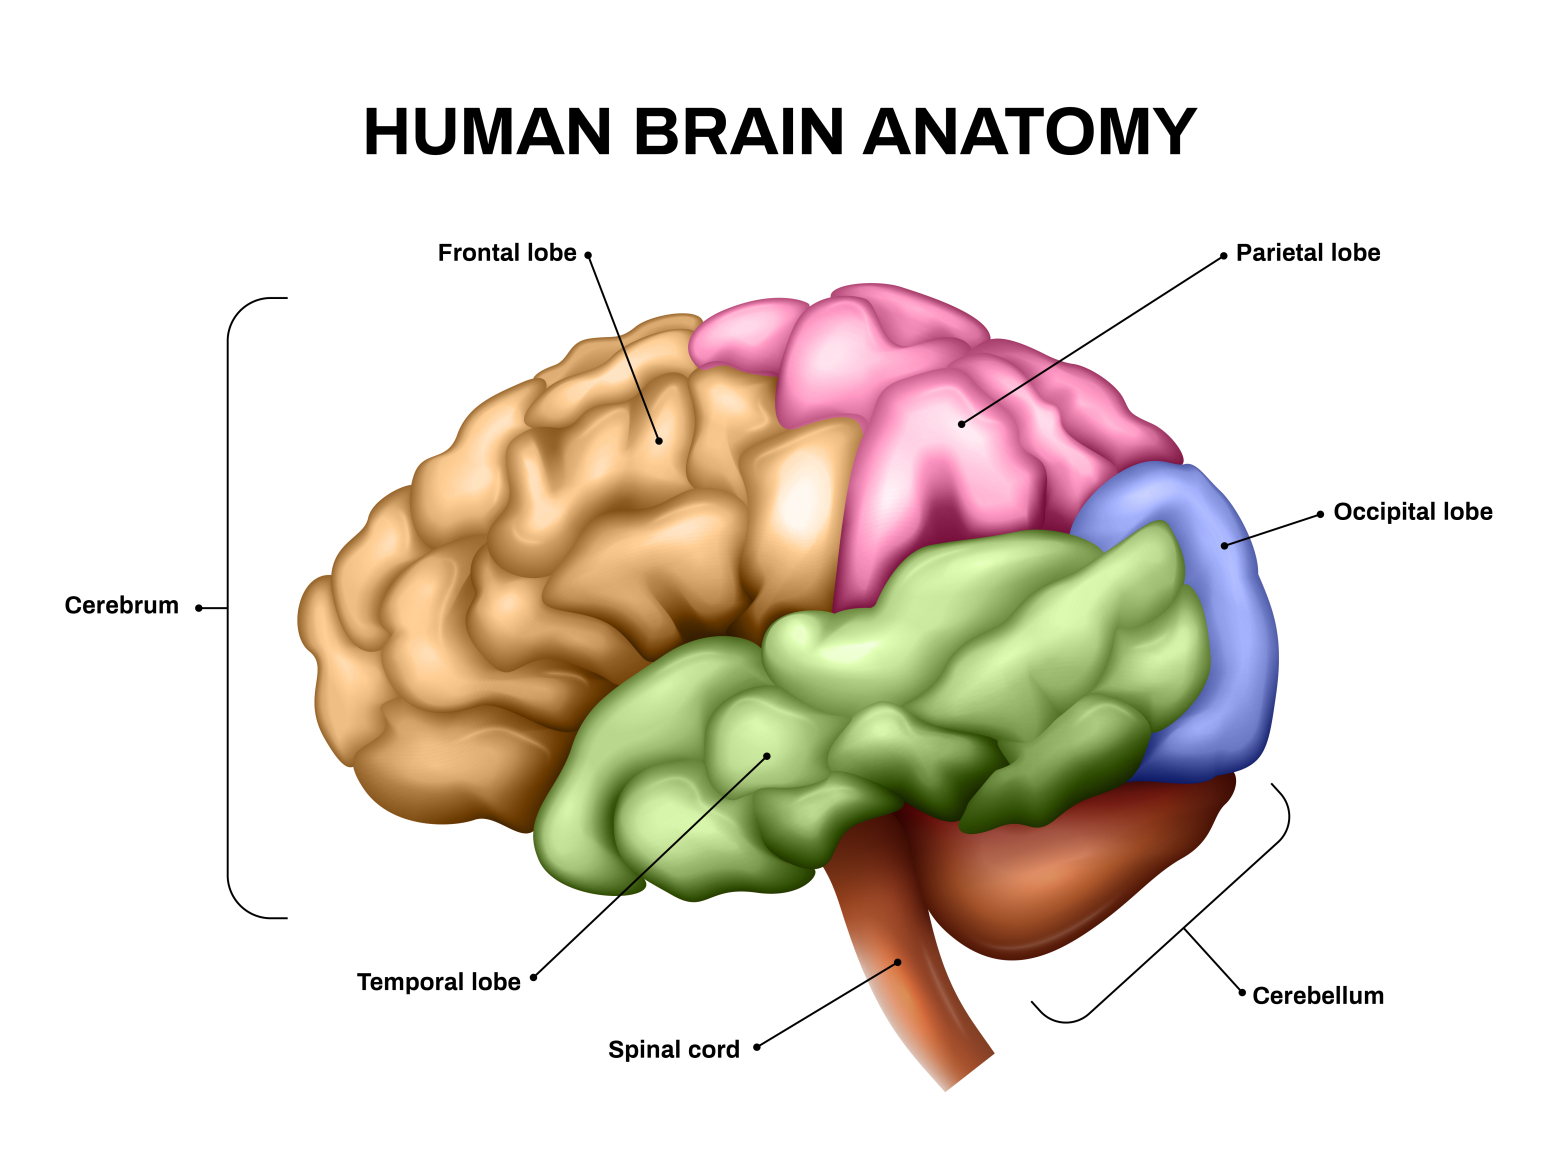

Легкие рисунки головного мозга: Пошаговые инструкции

Раздел: Житейские мотивы